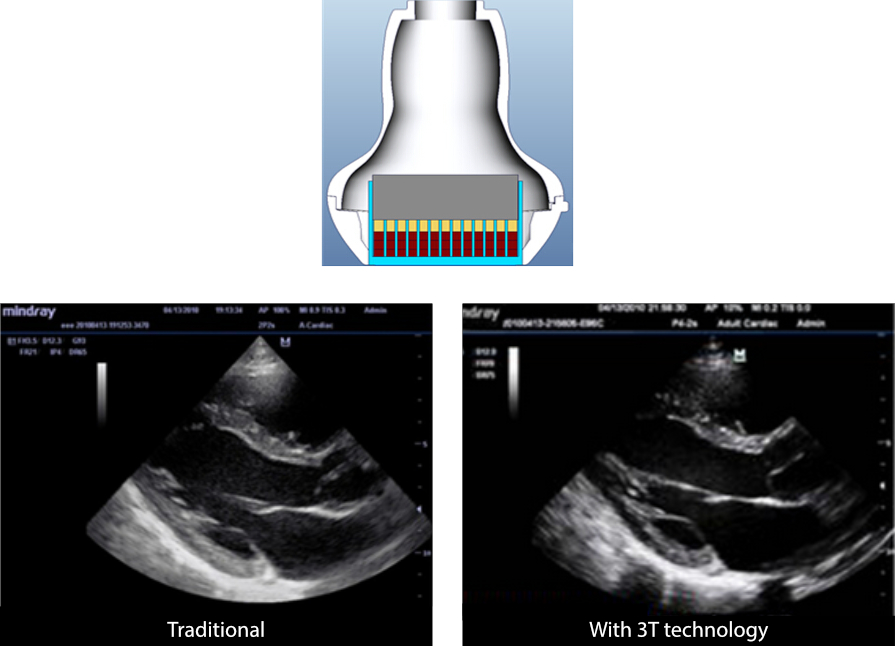

3T Transducer Technology?

Mindray'in g?rĂŒntĂŒ bant geni?li?ini ve iletim etkinli?ini art?rma ama?l?, patentli d?nĂŒ?tĂŒrĂŒcĂŒ teknolojisi.

· Daha yĂŒksek hassasiyet, daha yĂŒksek bant geni?li?i ve geli?mi? S/N i?in ĂŒ? e? katmanl? tasar?m

· Daha dĂŒ?ĂŒk ses k?prĂŒsĂŒ gĂŒrĂŒltĂŒsĂŒ, daha iyi y?nlendirme ve iyile?tirilmi? lateral ??zĂŒnĂŒrlĂŒk i?in tam kesimli tasar?m

· Daha iyi akustik iletim i?in ?s?l kontrollĂŒ tasar?m